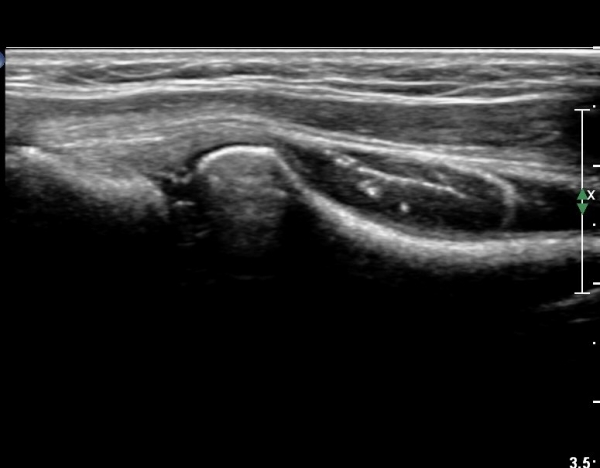

¿Ü»ó°ú¿¡¼­ ¼Õ¸ñ ½ÅÀü°Ç ´ÜµÎ Á¾´Ü¸é°Ë»ç¿¡¼­ ƯÀÌ ¼Ò°ßÀ» º¸ÀÌÁö ¾Ê´Â´Ù(»çÁø 1, 2)

¿ä°ñµÎ ºÎÀ§ ÆÈ²ÞÄ¡ ¾Õ, ¿ÜÃø Ⱦ´Ü¸é°Ë»ç¿¡¼­ Èİñ°£ ½Å°æ ³»Ãø, ¿ä°ñµÎ Ç¥Ãþ¿¡¼­

ÀÛÀº ³¶Á¾ÀÌ °üÂûµÈ´Ù(»çÁø 3)